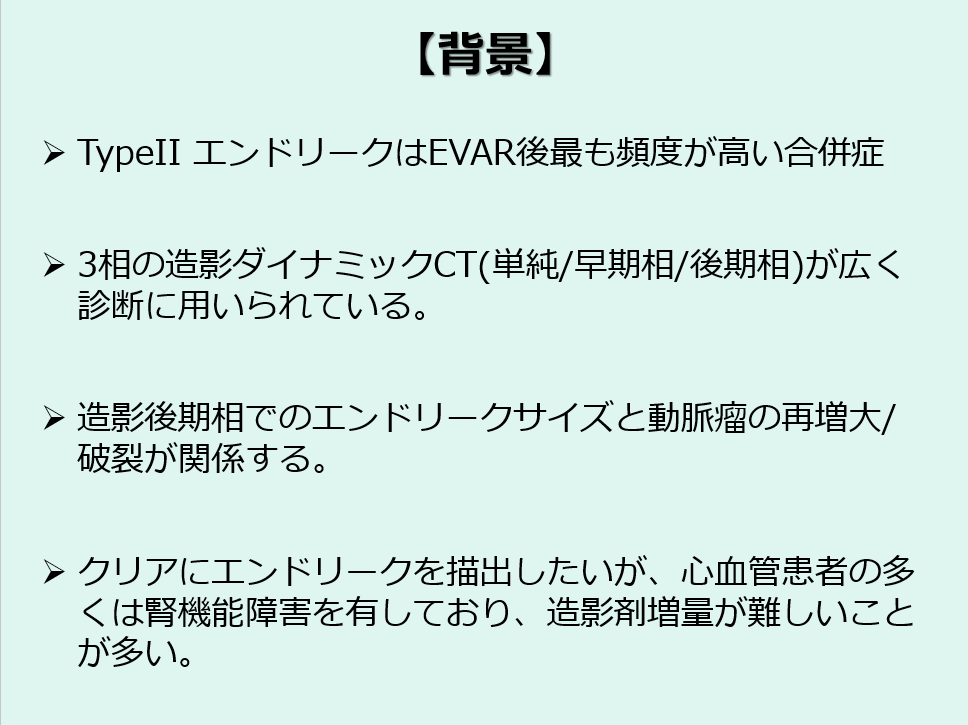

まず背景としてエンドリークはEVAR後最も頻度が高い合併症であり、特にTypeⅡの頻度が高くなっています。

エンドリークの評価としては3相の造影ダイナミックCTが広く用いられており、造影後期相でのエンドリークサイズが動脈瘤の再増大や破裂と関係するという報告もあります。

そのためエンドリークをクリアに描出したいところですが、造影後期相ではコントラストが不明瞭な場合も多く、また心血管患者の多くは腎機能障害を有しており、造影剤増量も難しいことが多いです。